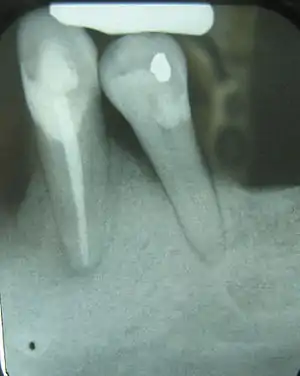

| Radiograph showing bone loss between the two roots of a tooth (black region). The spongy bone has receded due to infection under tooth, reducing the bony support for the tooth. | |